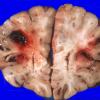

NEOPLASMS (HEMATOLYMPHOID)

Granulocytic Sarcoma (3)